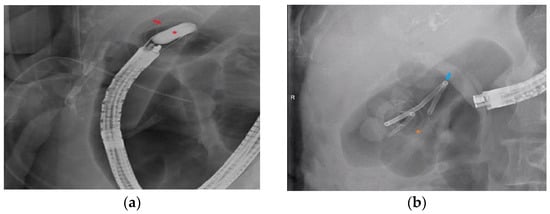

2.4. Procedure Detail